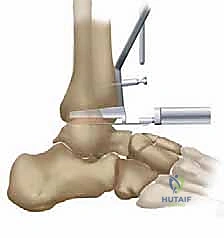

- Tibial Peg Cutting Guide Positioning: The tibial peg cutting guide is then carefully positioned on the anterior distal tibia.

TECH FIG 3 • Osteotomy of tibial anchor region. A. The tibial peg cutting guide.

Its superior and medial aspects are meticulously aligned with the prepared tibial surface and, crucially, with the talar trial component in place. This ensures the tibial component will articulate correctly with the talar component.

TECH FIG 3 • Osteotomy of tibial anchor region. B. The tibial peg cutting guide is inserted after placing the talar trial.

TECH FIG 3 • Osteotomy of tibial anchor region. C. Intraoperative view.

3. Tibial Anchor Preparation: The tibial anchor region is then prepared along the inner surface of this guide. This creates the precise cavity for the tibial component's anchoring mechanism.

TECH FIG 3 • Osteotomy of tibial anchor region. D. Reaming is completed.